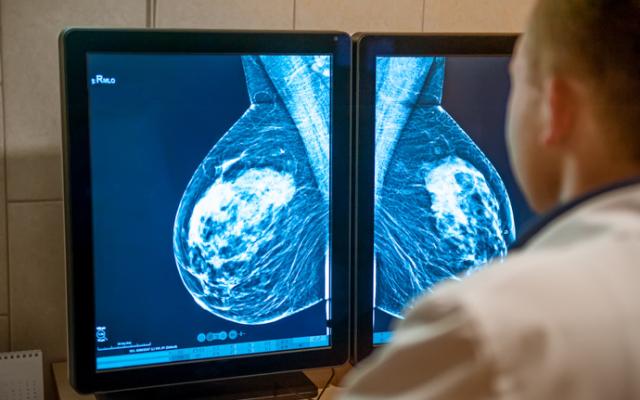

Mamografía y resonancia magnética

Con la mamografía se pueden ver quistes grandes y grupos de quistes pequeños, aunque no resulta muy útil para la detección de microquistes. En algunos casos, también se puede realizar una resonancia magnética (RM) mamaria, especialmente en mujeres con alto riesgo de cáncer, ya que este estudio ofrece imágenes más detalladas del tejido mamario.